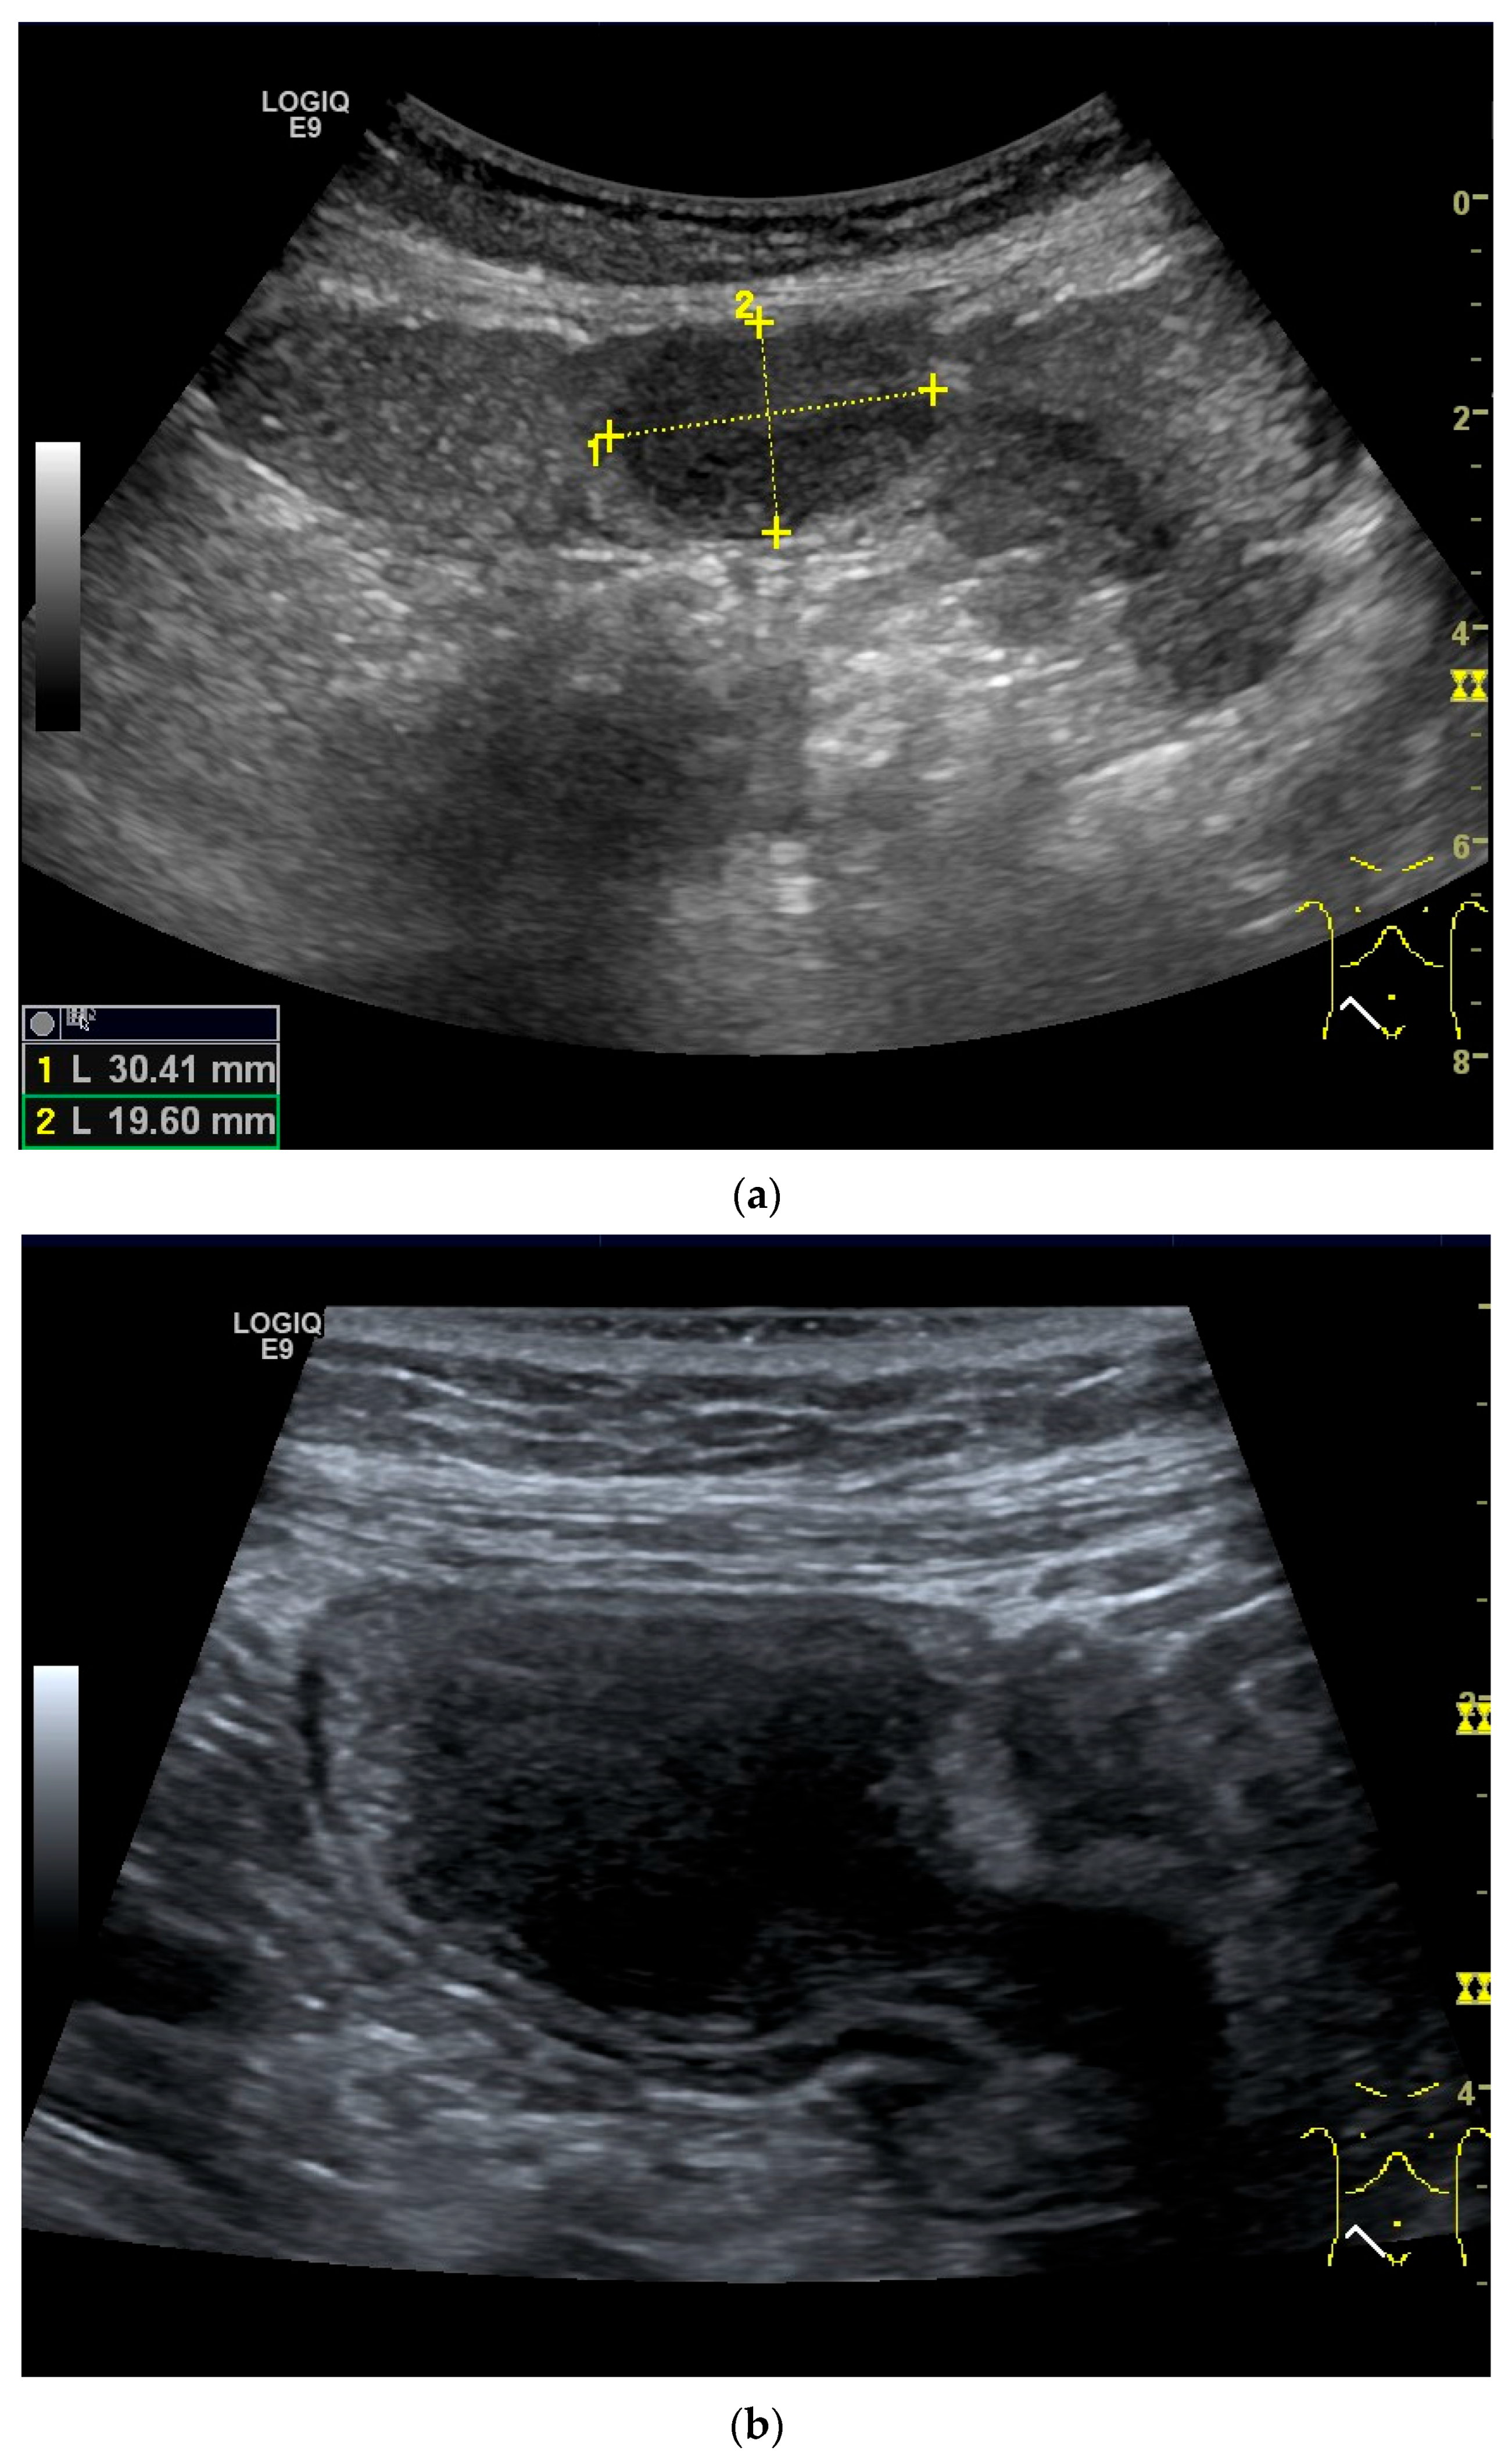

Figure 11.

GIST. A 30 mm large, very hypoechoic, almost anechoic round mass is visible in the left upper abdomen. This is located in the jejunum; the wall (W) and lumen (L) are visible (a). Macro vessels can be distinguished on Power Doppler, demonstrating that the lesion is solid and not cystic (b). On CEUS with 2.4 mL SonoVue (linear transducer 9 MHz), a small wheel-spoke-like vascular branching is visible at the margin (arrow) (c) with centrifugal enhancement (arrow) (d). Hyperenhancement is heterogeneous in the early arterial phase (e,f) and becomes homogeneous in the later course of the arterial phase (g). The extent of the heterogeneously enhanced tumor is marked with arrows (e). The intensity of the enhancement decreases during the first minute. The tumor is marked with arrows (h). Jejunal segment resection revealed the histology of an epithelioid GIST.

Figure 12.

GIST. Incidental finding of a 35 mm, slightly polycyclic, homogeneous hypoechoic mass in the left upper abdomen (a,b). This changes position with the movements of the small intestine. In CEUS with 1.2 mL SonoVue using the abdominal sector transducer (1–5 MHz), the mass shows homogeneous hyperenhancement in the arterial phase (c). The intensity then decreases (d). The tumor is marked with arrows in CEUS.